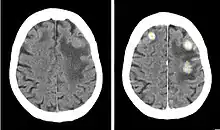

Iobitridol (trade name Xenetix) is a pharmaceutical drug used as an iodine-based radiocontrast agent in X-ray imaging.[1] It is injected into blood vessels, joints, or body cavities such as the uterus, and filtered out by the kidneys.[2] Its most common adverse effect is nausea. Severe allergic reactions are rare.[1][2]

Iobitridol is an iodine-containing radiocontrast agent.[2][5] The iodine atoms readily absorb X-rays, resulting in better contrast in radiography images.[9] The quality of images made with this drug is equally good as with other low– or medium–osmolarity iodinated contrast agents such as iopamidol or iohexol.[5]